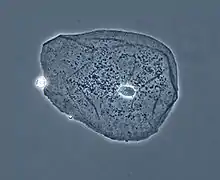

Le microscope à contraste de phase est un microscope qui exploite les changements de phase d'une onde lumineuse traversant un échantillon.

Le microscope à contraste de phase est très utilisé en bactériologie grâce à sa particularité de révélation des objets peu opaques, notamment dans le domaine dentaire dans la recherche en parodontologie, recherche de la flore bactérienne de la gencive pour détecter et suivre la maladie parodontale ou parodontite.